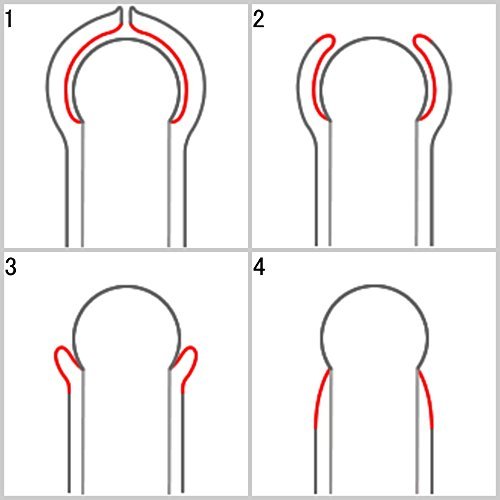

HOW TO USE 1. Insert the tips of the tool into the opening of your foreskin. 2. Squeeze the grips and expand the foreskin painlessly. 3. Hold this position for 15 minutes. 4. Continue 2 weeks every morning and evening. CAUTION Too much expanding can damage your foreskin. REFUND You will get a full refund if you are not satisfied with it. You can cure your phimosis by yourself at home. Without Circumcision. Phimosis treatment cures your tight foreskin. ring cream stretching kit correction penis.